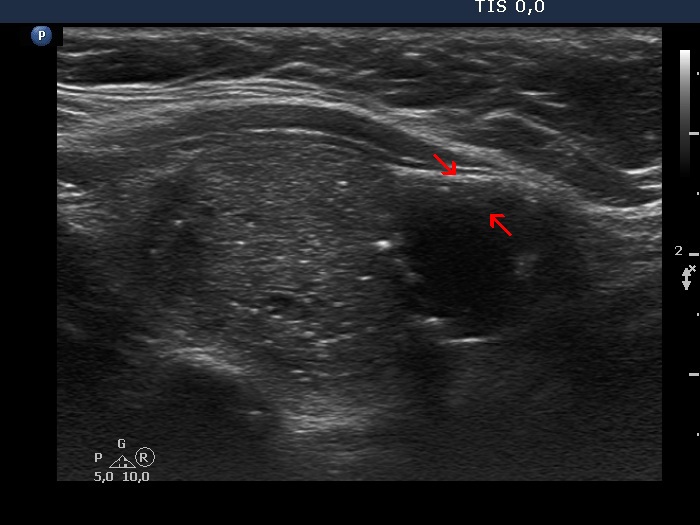

The composition of the nodule - case 1033

Examination 7 years later (ultrasonographic picture 5b)

Left lobe, longitudinal scan. The solid area marked with red arrows is the continuation of the larger, similarly moderately hypoechogenic lesion. On this observation, I mean that this is more probably a solitary, dominantly solid nodule than two nodules.